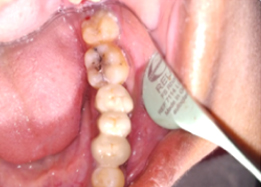

Hemisectomy

Post-OP Clinical View

PRE OP Clinical Photograph Measuring Probing Depth